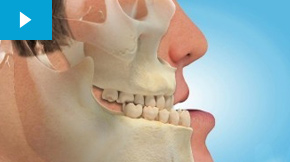

- عکس نیمرخ صورت (برای ارتودنسی)؛ این عکس نمای جانبی صورت را نشان میدهد و به بررسی وضعیت قرارگیری فکها، زاویه استخوانها و همچنین موقعیت کلی دندانها کمک میکند.

از تصاویر دندانی در درمان ارتودنسی برای بهدست آوردن اطلاعات دقیق و جامع درباره وضعیت فک و دندانها استفاده میشود. یکی از مهمترین این تصاویر، عکس نیمرخ صورت است که نقش بسیار کلیدی در تشخیص و برنامهریزی درمان دارد. با بررسی این نوع عکسها، متخصص ارتودنسی میتواند بهراحتی موارد زیر را تشخیص دهد:

- جلو یا عقب بودن فک بالا یا پایین

- انحراف فک یا بههمریختگی کلی در ساختار دندانها

- زاویه رشد دندانها و نحوه قرارگیری آنها نسبت به یکدیگر